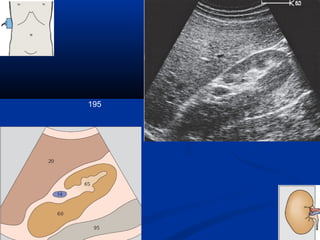

195